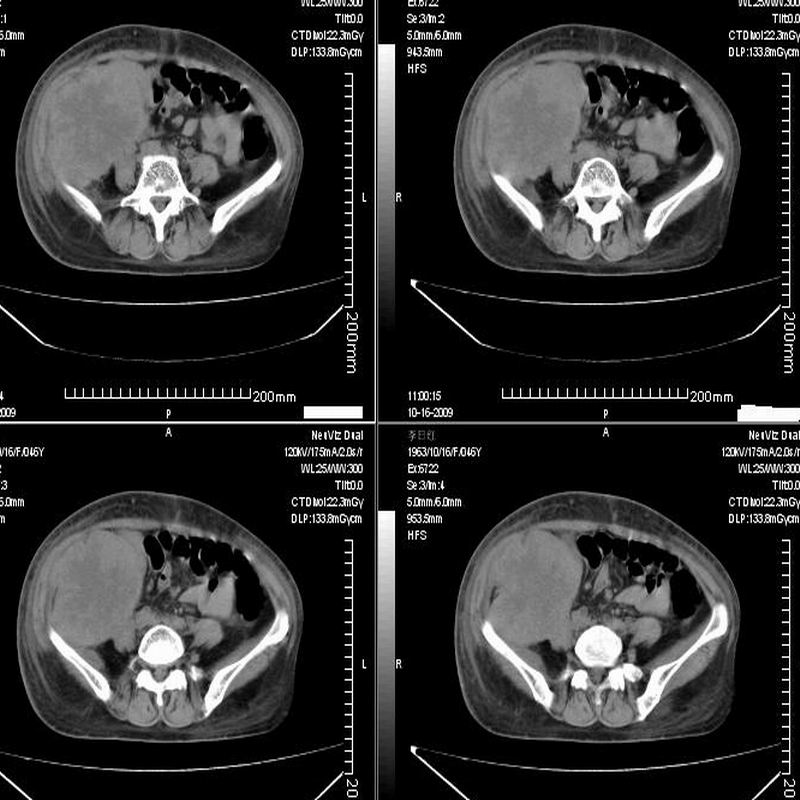

女:46y:一年前宫颈癌术后,现右下腹抚及肿块。

考虑宫颈癌术后复发周边侵犯/右中下腹及双侧腹股沟淋巴结转移。